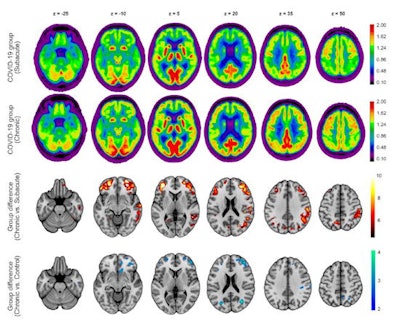

Group analysis using statistical parametric mapping revealed a widespread increase of F-18 FDG uptake in frontoparietal and, to a lesser extent, temporal neocortical regions in patients in the chronic stage compared to the subacute stage. No regions with significant decrease in glucose metabolism were identified. Voxel-wise comparison of chronic-stage patients to the age-matched control cohort confirmed the presence of a remaining neocortical hypometabolism in COVID-19 patients even at the chronic stage at an exploratory statistical threshold.

Results of the F18-FDG PET group analysis. First and second row: Transaxial sections of group averaged, spatially normalized F-18 FDG PET scans in patients at the subacute and chronic stages. Third and fourth rows: Regions that show significant increases of normalized F-18 FDG uptake in patients at the chronic compared with the subacute stage. Fourth row: Regions that still show significant decreases of normalized F-18 FDG uptake in patients at the chronic stage compared with the age-matched control cohort (two-sample t test, p < 0.005). Statistical parametric mapping t-values are color coded and overlaid onto an MRI template. Images are presented in neurologic orientation: the left image side corresponds to patients' left body side; numbers denote axial (Z) position in mm. Image courtesy of the Journal of Nuclear Medicine.Performance on the MoCA test significantly improved over time, from a mean global score of 19.1 ± 4.5 (maximum 30 points) at the subacute stage to 23.4 ± 3.6 at the chronic stage; however, the scores were still below the frequently used cutoff value for detection of cognitive impairment (< 26/30), according to the authors. Five of eight patients were still below this threshold. MoCA scores showed that orientation and attention were almost unimpaired at the chronic stage, but they revealed persistent deficits in visuoconstructive and executive functions and, especially, memory.